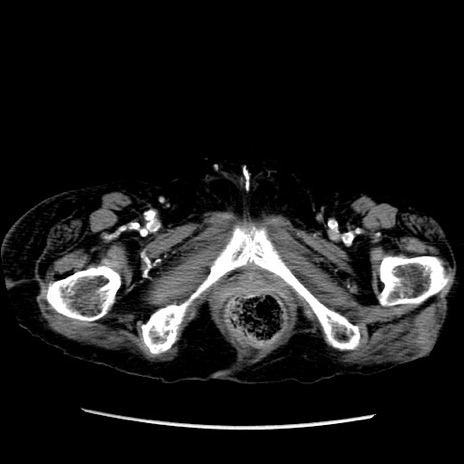

症例14(横断像)

【症例】 90歳代女性

【主訴】 腹痛・嘔吐

【現病歴】今朝から左側腹部痛を認めた。 経過観察していたが、嘔吐を認めたため来院。

【既往歴】 子宮癌術後

【身体所見】 意識清明、BP 127/54mmHg、P 98bpm Sp02 95%(RA)、BT 35.8°C、腹部平坦・軟腸ぜん動音聴取良好、右下腹部圧痛(+) 反跳痛なし

【データ】WBC 9800、CRP 0.46